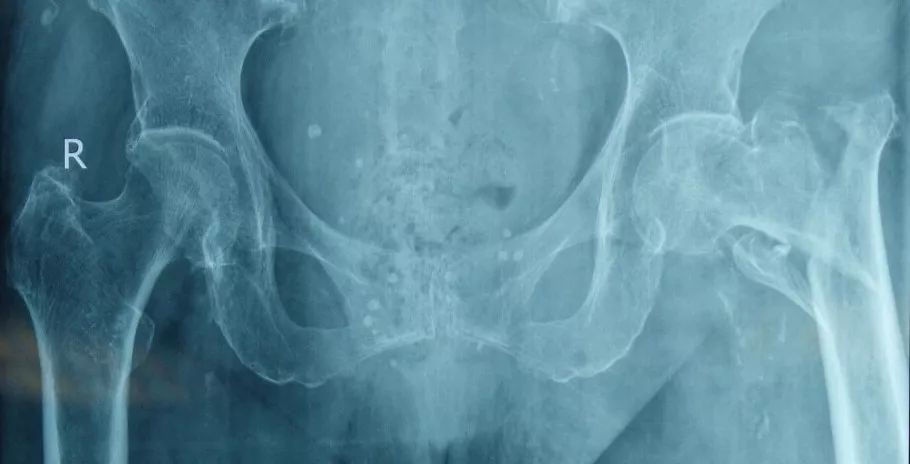

这是一个股骨粗隆间骨折的老年患者,和其他人一样,也是走路时不小心摔倒导致骨折,骨折移位明显,而且有较大的骨碎块。

外院医生给这位患者做了骨折内固定手术,可以看到骨折对位良好,骨碎块未作特殊处理。

术后病情稳定转至我院进行康复治疗,早期即给予双下肢床上主动及被动功能训练。